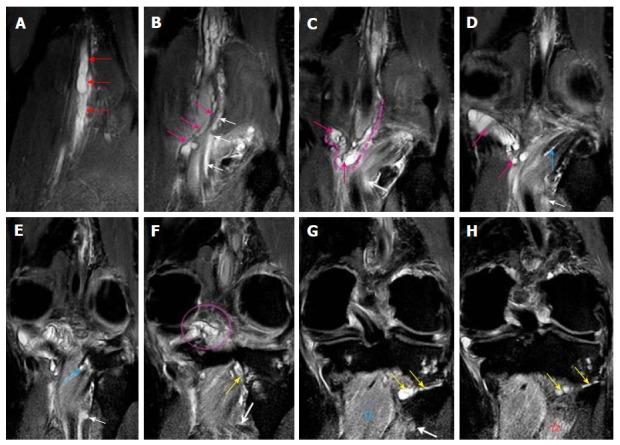

A retrospective analysis of the magnetic resonance (MR) images of a cohort of 245 patients presenting with nerve palsy involving different peripheral nerves was done. MR images were analyzed for the presence of a nerve lesion, and if found, it was further characterized as solid or cystic. The serial axial, coronal and sagittal MR images of the lesions diagnosed as INGC were studied for their pattern and the anatomical extent along the course of the affected nerve and its branches. Its relation to identifiable anatomical landmarks, intra-articular communication and presence of denervation changes in the muscles supplied by involved nerve was also studied.

A total of 45 cystic lesions in the intra or extraneural locations of the nerves were identified from the 245 MR scans done for patients presenting with nerve palsy. Out of these 45 cystic lesions, 13 were diagnosed to have INGC of a peripheral nerve on MRI. The other cystic lesions included extraneural ganglion cyst, paralabral cyst impinging upon the suprascapular nerve, cystic schwannoma and nerve abscesses related to Hansen's disease involving various peripheral nerves. Thirteen lesions of INGC were identified in 12 patients. Seven of these affected the common peroneal nerve with one patient having a bilateral involvement. Two lesions each were noted in the tibial and suprascapular nerves, and one each in the obturator and proximal sciatic nerve. An intra-articular connection along the articular branch was demonstrated in 12 out of 13 lesions. Varying stages of denervation atrophy of the supplied muscles of the affected nerves were seen in 7 cases. Out of these 13 lesions in 12 patients, 6 underwent surgery.